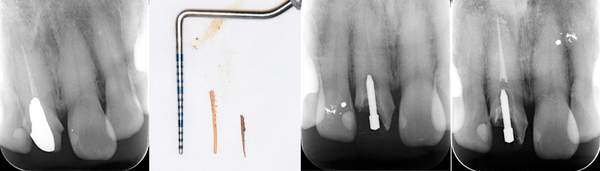

根の中の白い縦の線がなくなっています。これは、中に詰まっていた、防腐剤を取り除いた証拠になります。取り除いてから、根の中をしっかり清掃していきます。

清掃が終わり、患者様も違和感がなくなったということで、防腐剤を再び詰めていきました。最初に入っていたものと比較して緊密に太く入っているのがわかります。

根の中に入っていた防腐剤を取り除いた時の写真です。感染物質が付着して黒くなっているのがわかります。

また、防腐剤をとりのぞけても、その防腐剤を歯の根のなかにくっつける素材が残っていますので、それもしっかり取り除きます。

こちらは根の途中までしか防腐剤がはいってませんでした。患者様が違和感を訴えたため、治療を行いました。防腐剤を取り除き、根の中を清掃し、根の先端までしっかり防腐剤をいれました。